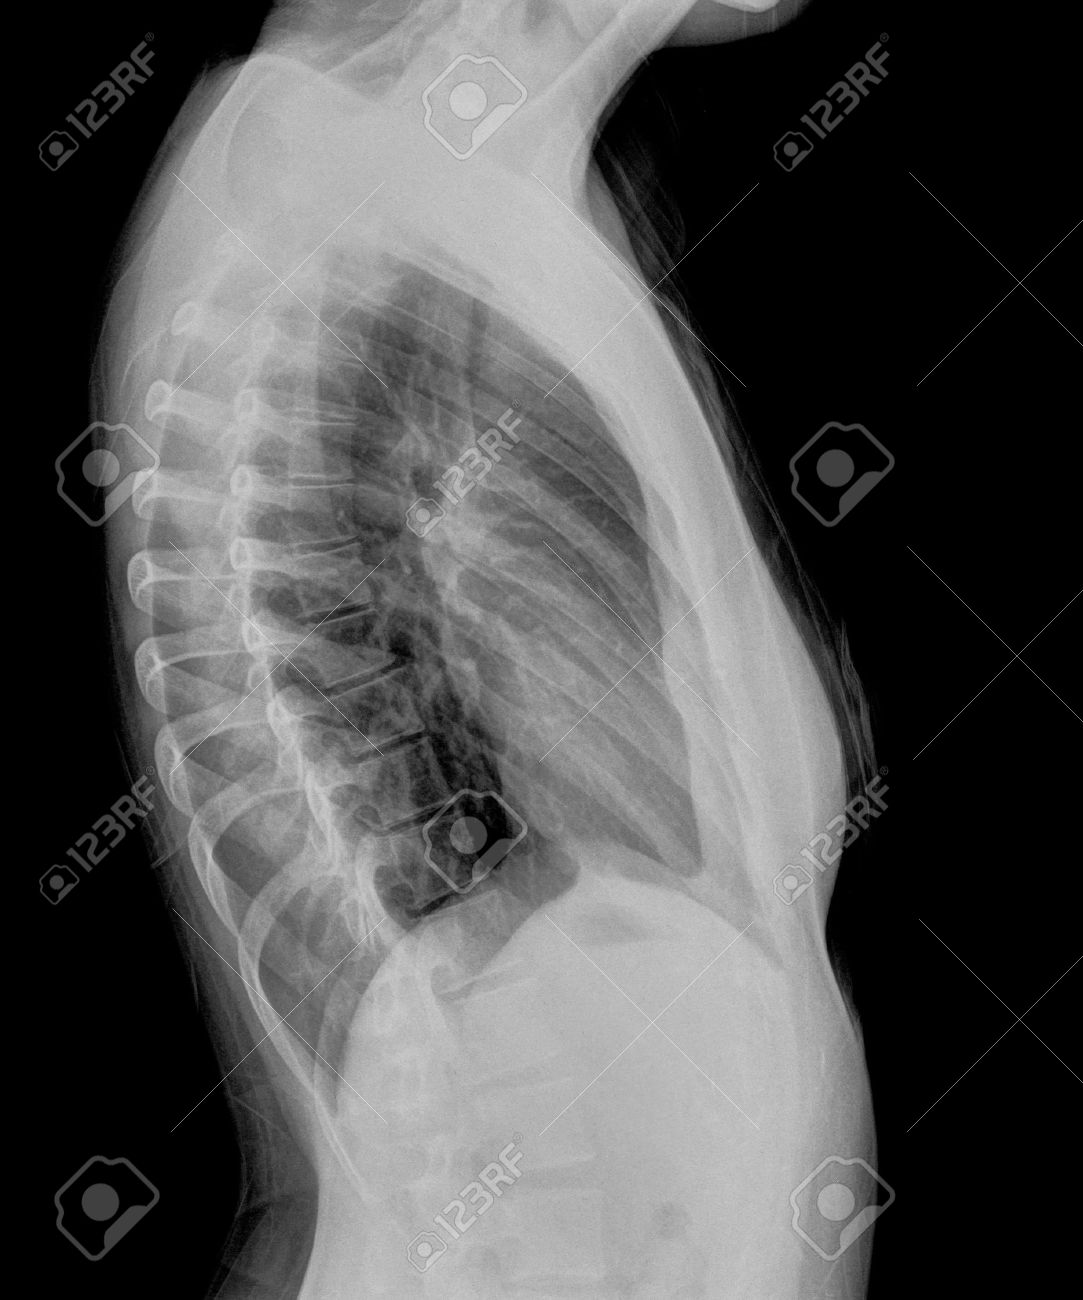

Manifestaciones Radiológicas

ásicamente se ha dividido la TB en primaria (TBp) y secundaria (TBs) o postprimaria. La TBp se presenta en pacientes sin contacto previo con el bacilo y la TBs en pacientes que, habiendo desarrollado ya una hipersensibilidad frente al germen, sufren un nuevo contagio o, lo que es mucho más frecuente, una reactivación de alguna de las lesiones residuales de la primoinfección. Es importante recordar que en cuanto se desarrolla la hipersensibilidad celular en la TBp, generalmente a partir de la cuarta semana o si el paciente ha sido previamente vacunado con la BCG, las lesiones radiológicas que vamos a observar van a ser muy parecidas a las de la TBs. Por el contrario la TBs desarrollada en un paciente con severa depleción de los linfocitos T, como en las fases avanzadas del SIDA va a tener el perfil de una TBp.

Cuatro son los patrones radiológicos que suelen describirse en la TBp: la TB gangliopulmonar, la TB pleural, la TB miliar y la TB traqueobronquial. En realidad los tres últimos pueden observarse igualmente en la TBs y se describirán conjuntamente.